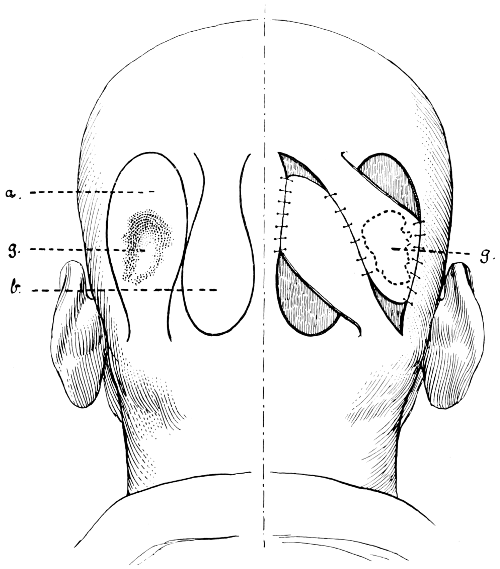

Fig. 1. Cranio-cerebral Topography. 1, The nasion; 2, The inion; 3, The mid-point between nasion and inion; 4, The Rolandic fissure; 5, The superior temporal crest; 6, The inferior temporal crest; 7, The Sylvian point; 8, The anterior horizontal limb of the Sylvian fissure; 9, The vertical limb of the Sylvian fissure; 10, The posterior horizontal limb of the Sylvian fissure; 11, The parietal prominence; 12, The malar tubercle; 13, The lambda; 14, The first temporo-sphenoidal sulcus; 15, The external parieto-occipital sulcus; 16, The lateral sinus; 17, 17, 17, The level of the base of the cerebrum; 18, The external auditory meatus; 19, 19, Reid’s base-line. (Reproduced, by the permission of Mr. H. K. Lewis, from the author’s work on ‘Landmarks and Surface-markings’.)

Fig. 2. Cranio-cerebral Topography. 1, 1, Reid’s base-line; 2, 2, A line parallel to the above at the level of the supra-orbital margin; 3, The middle meningeal artery; 4, The anterior branch; 5, 5, 5, The three sites for trephining; 6, The posterior branch; 7, The site for trephining; 8, The point for trephining to reach the descending horn of the lateral ventricle; 9, The lateral sinus; 10, The inion; 11, The mastoid process; 12, Macewen’s suprameatal triangle; 12a, The mastoid antrum; 12b, The facial nerve; 13, The suprameatal and supramastoid crests; 14, 14, The temporal crest; 15, The temporal fossa; 16, The external angular frontal process; 17, The tendo-oculi attachment; 18, The lachrymal groove. (Reproduced, by the permission of Mr. H. K. Lewis, from the author’s work on ‘Landmarks and Surface-markings’.)